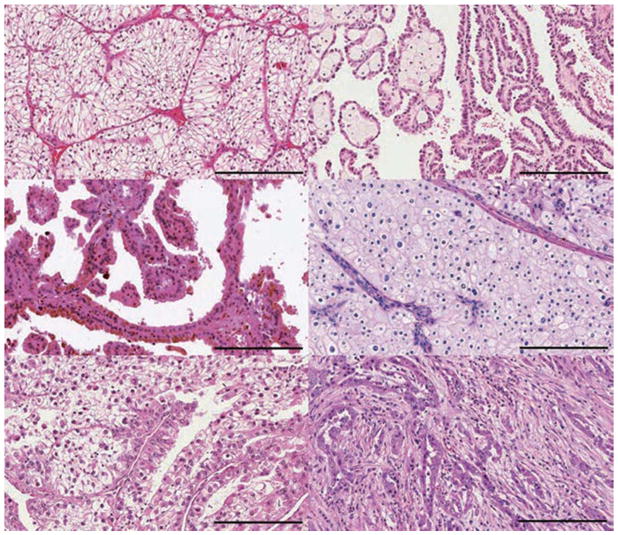

大约 75% 的肾细胞癌 (RCC) 是 a: 透明细胞 RCC (ccRCC)。 b | 乳头状 RCC 约占所有肾癌的 15%,根据染色特征分为两种类型:b | 1 型(嗜碱性)和 c | 2 型(嗜酸性)。 d | 嫌色细胞 RCC 约占肾肿瘤的 5%。 其他次要亚型包括 e | MiT 家族易位 RCC 和 f | 集合管 RCC。 其他次要亚型包括髓质 RCC、透明细胞乳头状 RCC、获得性囊性病变相关 RCC、肾小管囊性 RCC、粘液性管状和纺锤体 RCC、琥珀酸脱氢酶缺陷型 RCC、遗传性平滑肌瘤病、肾细胞癌相关 RCC 和嗜酸细胞瘤。 不属于这些类别的肿瘤被指定为未分类 RCC。 比例尺 = 200 微米。